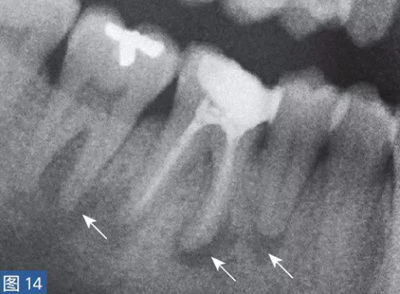

放射學(xué)檢查是診斷根尖周炎的一個(gè)重要工具。當(dāng)然,也存在多種類似于牙髓源( endodonticorigin)病變的X 線透射和阻射病變,這其中包括例如外傷、異物反應(yīng)、埋伏的遷移殘根和良性或者惡性纖維骨性腫瘤。根尖周炎也可能擴(kuò)散至鄰牙,這對(duì)應(yīng)著一個(gè)獨(dú)立的根尖周炎影像(圖14 和15)。為了獲得準(zhǔn)確的診斷,還要進(jìn)行臨床檢查,包括了解患者的癥狀及病史,并與放射學(xué)檢查結(jié)果進(jìn)行比較。

圖14:鑒別診斷。第4 象限的術(shù)前影像(取自全景片的放大圖像)?;颊吒杏X在第IV象限區(qū)的牙齒存在大范圍的不適癥狀。放射學(xué)檢查顯示, 45-47 牙齒可見透影區(qū)。臨床檢查,觸診和叩診45-47 牙齒疼痛明顯。46 牙齒的牙髓電活力測(cè)試為陰性,47 和45 牙齒未顯示病理特征。